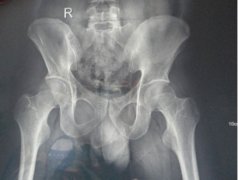

• 26岁小伙得强直在我院恢复健康

该患者的相关情况,由蒙兴文主任的助理医生跟踪记录,内容属实 ...